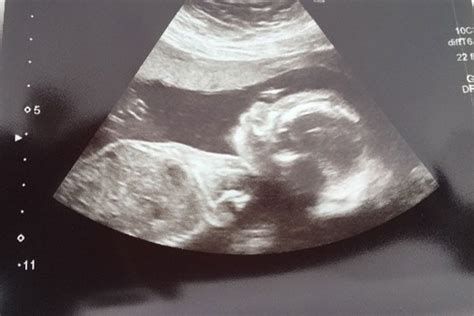

Hey guys, let’s talk about something super important and, let’s be honest, a bit nerve-wracking: the 20-week anatomy scan. This is usually a really exciting milestone in your pregnancy, where you get to see your little one in more detail, maybe even find out their gender! But sometimes, unfortunately, this scan can bring unexpected and difficult news. If you’re facing this, know you’re not alone, and we’re here to break down what might happen and how to navigate it. This scan, often called the mid-pregnancy ultrasound, is a comprehensive check of your baby’s development. The sonographer meticulously examines every part of your baby’s body, from their head to their toes, looking for any signs of potential issues. They check the brain, heart, lungs, kidneys, stomach, spine, and all four limbs. It’s a thorough review designed to catch any structural abnormalities or developmental concerns that might require attention before or after birth. While the vast majority of these scans come back with great news, showing a healthy, developing baby, it’s crucial to understand that the 20 week scan is also a diagnostic tool. This means it’s specifically looking for problems, and sometimes, it finds them. The reasons for concern can range from minor variations that won’t affect your baby’s health to more significant conditions that will need medical intervention. It’s a lot to take in, and the uncertainty can be incredibly stressful. Remember, the professionals performing the scan are highly trained, and they are looking for specific markers of development. If they see something that doesn’t quite fit the expected pattern, it’s their job to flag it for further investigation. It doesn’t automatically mean the worst-case scenario, but it does mean a closer look is needed. Trying to stay calm during this period is easier said than done, but try to focus on the fact that early detection is key to providing the best possible care for your baby. The 20 week scan is a powerful tool in that process, offering insights that can help you and your medical team prepare.